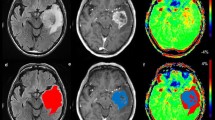

DCE-MRI data were analyzed using a valid method and the perfusion maps including cerebral hemodynamic (CBV and CBF), permeability (Ktrans, Kep, etc.), and semi-quantitative (IAUC60, Peak, etc.) indices were extracted. The exemplary maps achieved for a 57-year-old woman with glioblastoma multiforme (GBM) are shown in Fig. 1.

Exemplary maps achieved for a 57-year-old woman with right temporal glioblastoma multiforme (GBM). Axial post-contrast T1-weighted image shows an enhancing lesion in the right temporal lobe. Axial T2-weighted image shows an ill-defined mass with higher signal intensity than the normal brain tissue. The cerebral hemodynamic (CBV and CBF), semi-quantitative (IAUC60, Wash-in rate, and Peak), and permeability (Ktrans, Vb, and Ve except for Kep) maps have shown an enhancing lesion in the right temporal lobe. There is a well-discriminated border around the tumor